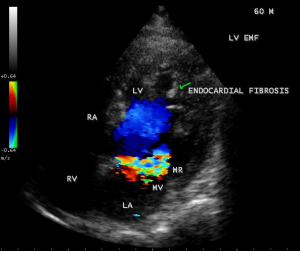

Case 8. Left ventricular endomyocardial fibrosis coexisting with RHD (rheumatic heart disease) in a 60-year old male as shown in Figures 27 and 28.

Figure 27: showing the thickening and calcification of mitral leaflets with flail Posterior mitral leaflet suggesting rheumatic involvement in a 60-year old male.

Figure 28: showing the mitral regurgitation due to PML (posterior mitral leaflet) involvement in a 60-year old male.